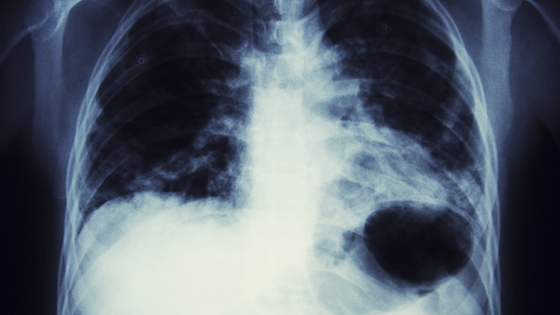

– Kan bli en ny kur mot lungekreft

Nanomedisin med gassbobler har vist seg å være en unik måte å transportere cellegift inn i lungene til kreftpasienter. Metoden gjør presis og konsentrert behandling mulig – og hindrer samtidig en rekke bivirkninger fordi den bare virker lokalt.